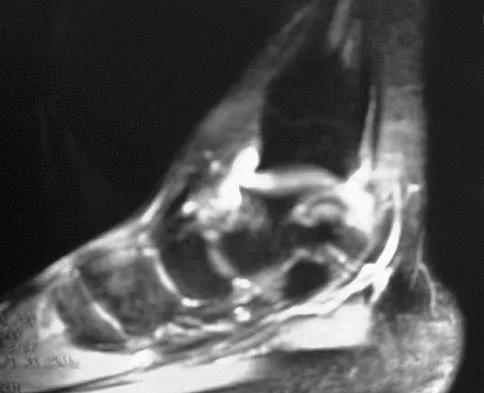

Figure 7 shows the MRI scan of a 23-year-old competitive rugby player who has anterior ankle pain and swelling. He states that he has been playing for many years and has sprained his ankle several times. Examination will reveal what specific hallmark feature?

Figure 7 shows the CT scan of a 25-year-old soccer player who has had posterior ankle pain with plantar flexion for the past 2 years. Immobilization has failed to provide relief. He is ambulatory. Management should consist of